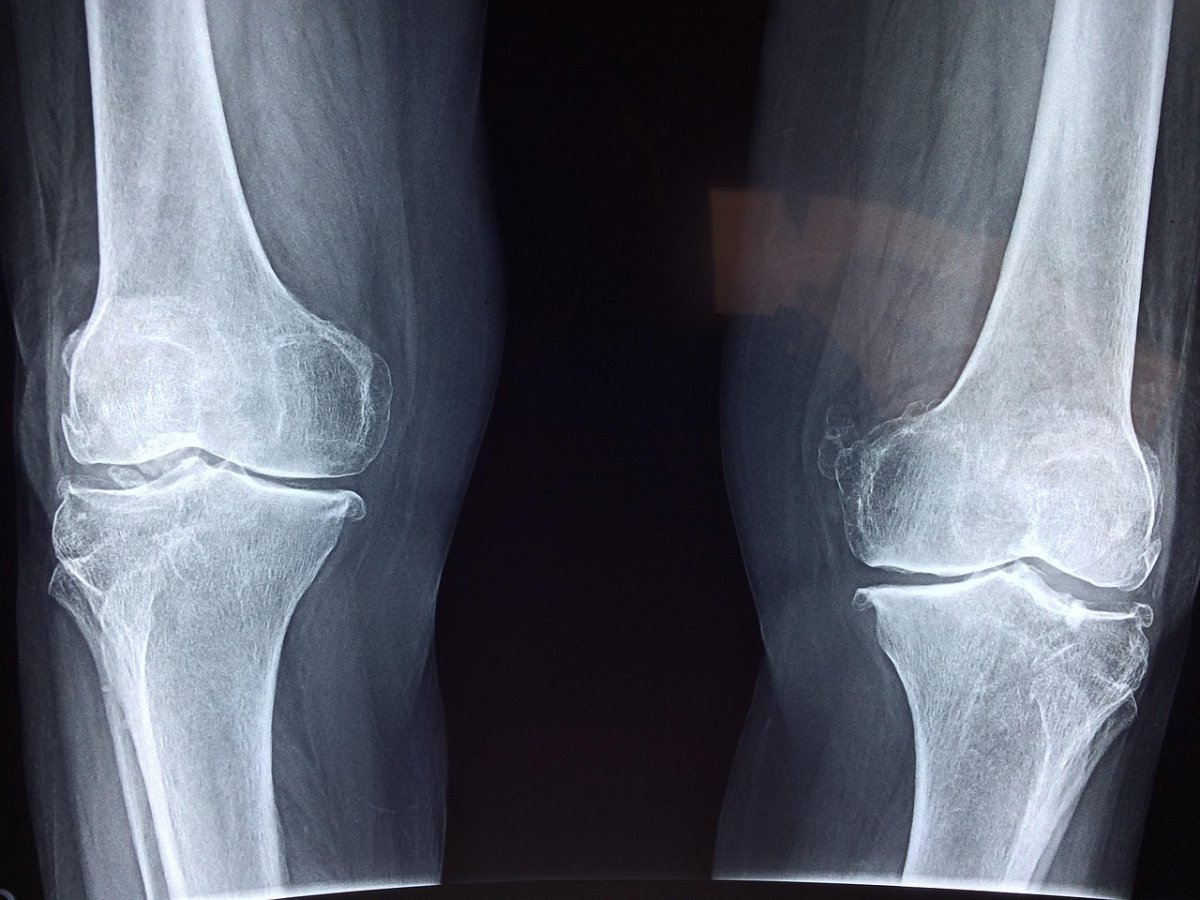

“Ребенок уже не ходил. У него была контрактура конечностей. Мы сделали первичную хирургическую обработку в экстренных случаях. Подготовили рану. На следующий день была также первичная хирургическая обработка с пересадкой кожи более 10 процентов одномоментно. Восстановление нервной системы и мышечного каркаса”, – отметил заведующий приемным отделением Центра детской неотложной медицинской помощи Мейржан Курманалиев.

В больнице мальчик провел две недели. Хирурги отмечают, если бы он приехал на несколько дней позже, то ногу пришлось бы ампутировать. Сейчас юный пациент проходит контрольные осмотры и поэтапную реабилитацию под наблюдением врачей.